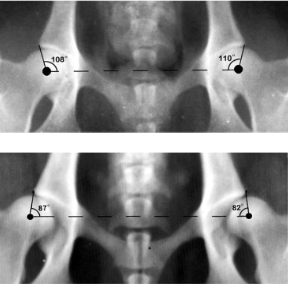

What is the Norberg-Olsson angle?

Angle used to assess hip dysplasia